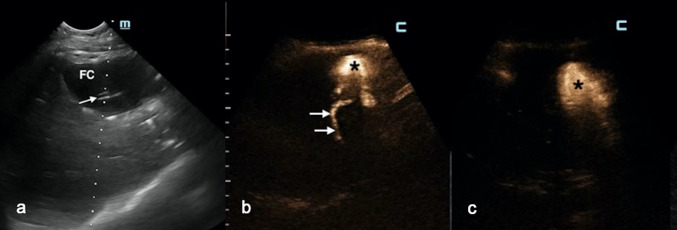

Fig. 6.

a Postoperative extrahepatic fluid collection (FC) with a catheter inside (white arrow). b After 2 days of continuous drainage, the fluid drained appeared stained with bile. IC-CEUS: a fistulous tract between the fluid collection (black asterisk) and the intrahepatic biliary tree (white arrows) was noted. c After endoscopic sphincterotomy, no bubble moved from the fluid collection (black asterisk) to the biliary tree (black liver)